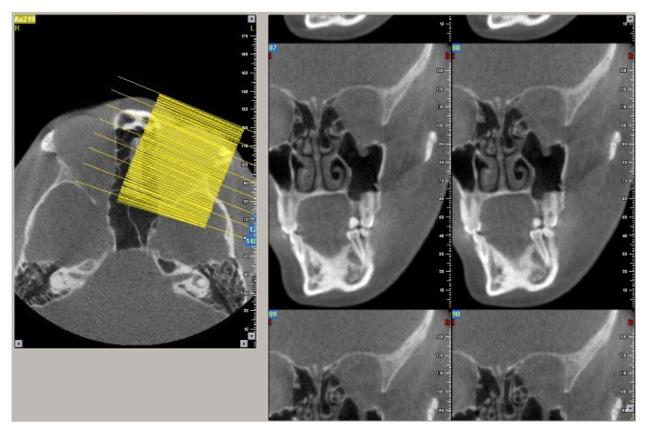

CBCT examination of the mid-face fractures area involving the floor of the orbit was performed in a number of 93 trauma patients by two independent radiologists. Both radiologists assessed the axial, coronal and sagittal sections and also the oblique coronal and sagittal extracted sections evaluating the location of the orbital fractures, its size and displacement, the involvement of the infra-orbital foramen, herniation of fat or muscle within the maxillary sinus, the overall type of the fracture and the implication of lateral or medial orbital wall. We also registered the section that provided better confidence of both examiners in visualizing the fracture of the orbit floor and the presence of herniated soft tissue, on different reformatted sectioning.

The presence of pure fracture of the orbital floor was detected in 11% of patients. The association of the orbital fractures with the zygomatic fractures was identified in the majority of the patients. In 86% of patients the displacement of the floor of the orbit was visualized, and in almost 30% of cases more than 50% of the orbital floor was involved in the fracture. Regarding the confidence between examiners, they were more confident using the oblique sagittal CBCT reformatted images for fracture detection and bone displacement evaluation, as for the soft tissue herniation the oblique coronal sections provided the highest level of confidence.

Mid-face trauma involves the orbital floor in the majority of situations. CBCT allows to obtain oblique images extracted from the three dimensional (3D) data that provide high confidence level in assessing pure orbital floor fractures.